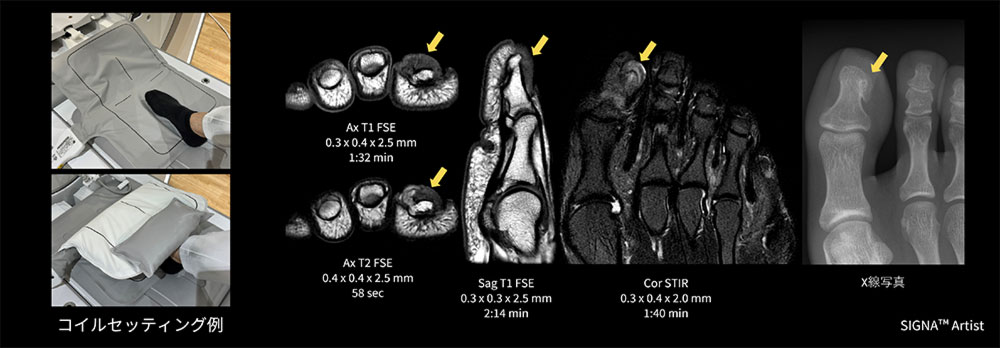

10代の女性。半年前から第1足趾に痛みがあり足趾の爪甲部下に結節の出現と爪甲の変形がみられたためMRI検査を実施。結節サイズが8mmほどと小さかったので、MP Coilで足趾を挟むようにポジショニングを行った。

母趾末節骨足背内足部から足尖足背方向に突出構造あり、内部の骨髄様構造が末節骨構造と連続、軟骨帽様構造を認めることから、骨軟骨腫、外骨腫疑いとなった(図8)。

画像の様にコイルで挟むだけで足趾に合わせたFOVでの撮像が可能で、連続する骨髄の描出が出来た一例。

AirCoils_Shigaikadai_09.jpg図8 爪下腫瘤検査におけるMP Coilのセッティング例と臨床画像